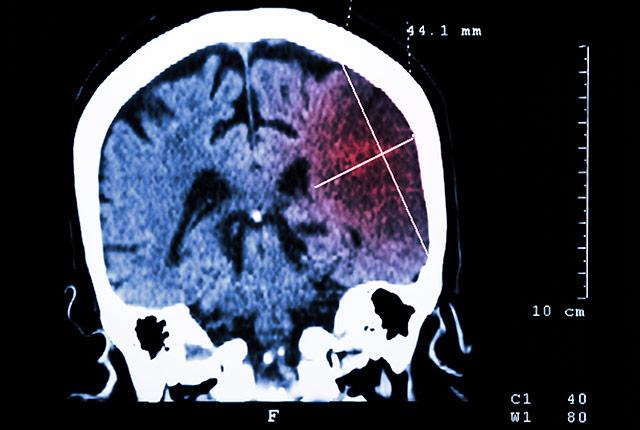

New study reveals ‘startling’ risk of stroke

Globally, one in four people over age 25 is at risk for stroke during their lifetime, according to a new scientific study.